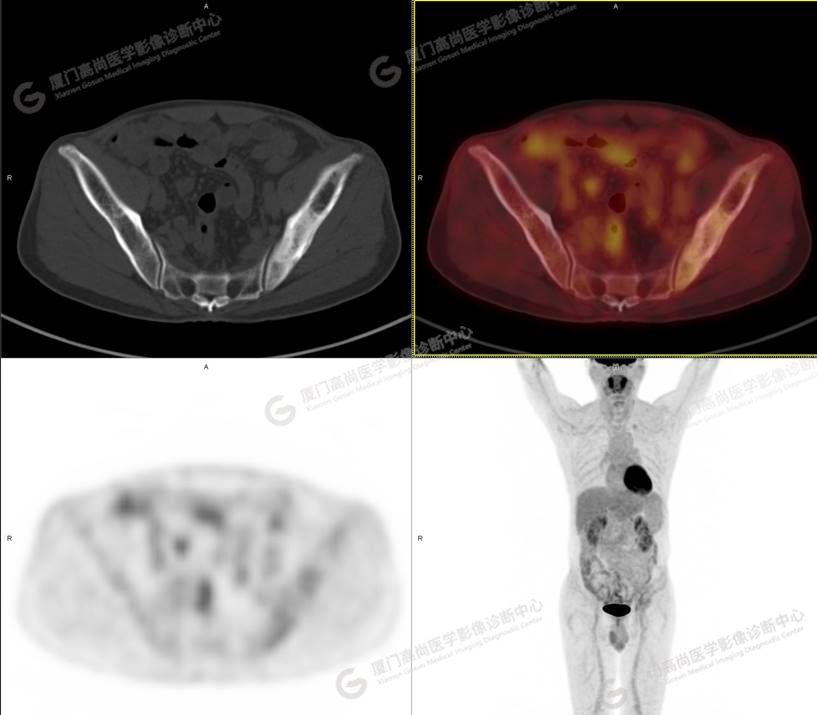

病史摘要1

60歲的L先生,因“左側(cè)臀部疼痛伴行走困難3月余”就診,外院核素骨顯像示:左側(cè)髂骨顯像劑增加,考慮惡性病變可能。同時實驗室檢查發(fā)現(xiàn)腫瘤指標(biāo)糖類抗原724稍增高。談癌色變!驚恐的L先生選擇了腫瘤檢查的核武器——PET/CT以探明虛實。

PET/CT檢查

PET/CT所見:左側(cè)髂骨、髖臼及恥骨骨質(zhì)密度不均勻增高,CT值約594Hu,邊緣模糊,放射性攝取輕度增高,SUVmax 2.79,周圍軟組織未見明顯異常。

影像診斷: L先生和Z女士的骨骼改變,指向了同一個疾?。汗抢w維異常增殖癥。